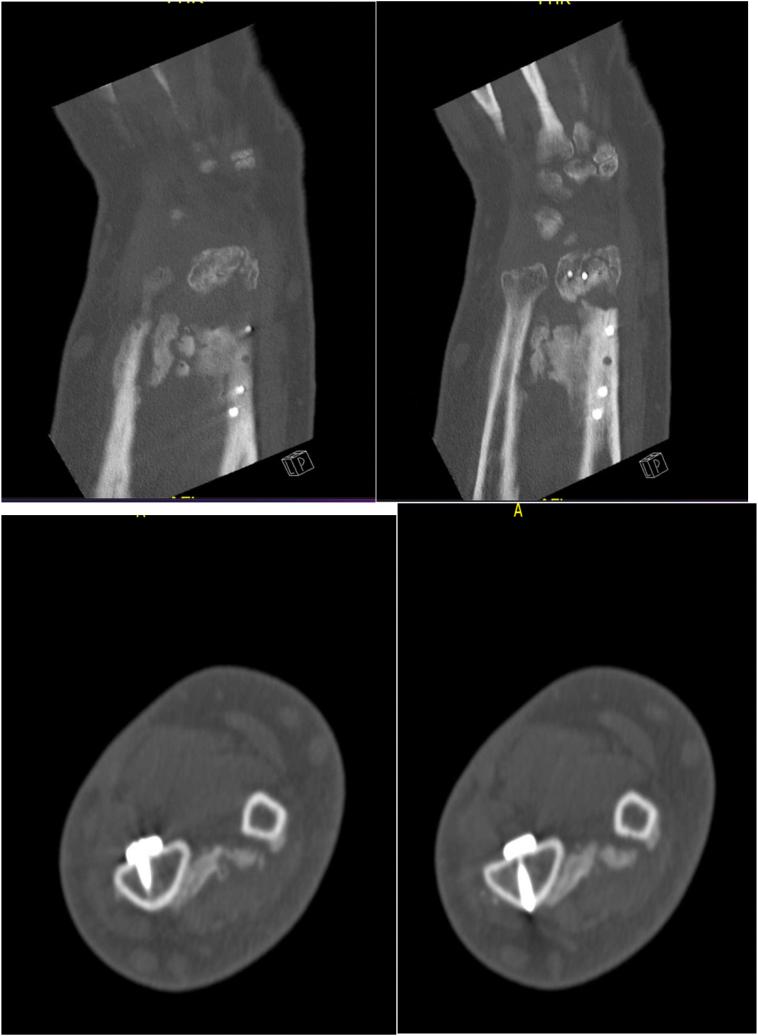

A 57-years old man who sustained left distal radius fracture. We performed distal radius ORIF. At follow up visit, he could not achieve any supination-pronation movements. Radiographs showed radioulnar synostosis. Four months later, we performed excision of synostosis with interposition of fat graft in the left forearm. A year later, the patient showed good forearm pronation and supination.

一名57岁男性,左侧桡骨远端骨折。我们对其进行了桡骨远端切开复位内固定术。在随访时,他无法进行任何旋前-旋后运动。X线片显示桡尺骨融合。四个月后,我们在左前臂进行了融合骨切除并植入脂肪移植。一年后,患者前臂旋前和旋后功能良好。